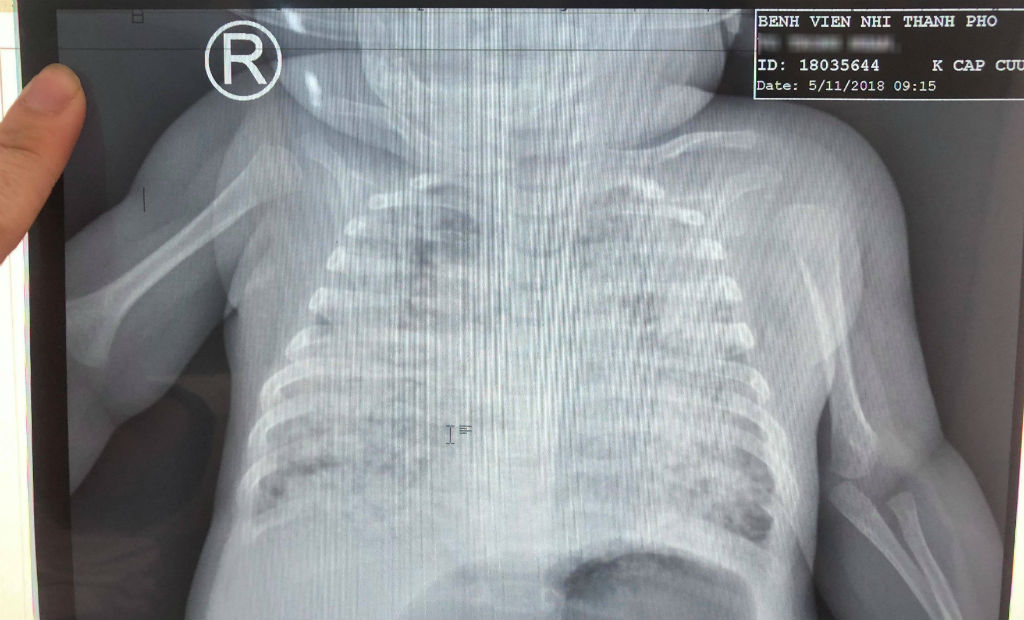

Phổi bệnh nhi trắng xóa quá phim chụp Xquang

Theo BS, phổi của bé trai trắng xóa, kén khí do các ổ lao vỡ tấn công khiến bệnh nhi bị tràn phổi 4 lần, suy hô hấp nặng, phải thở máy liên tục.